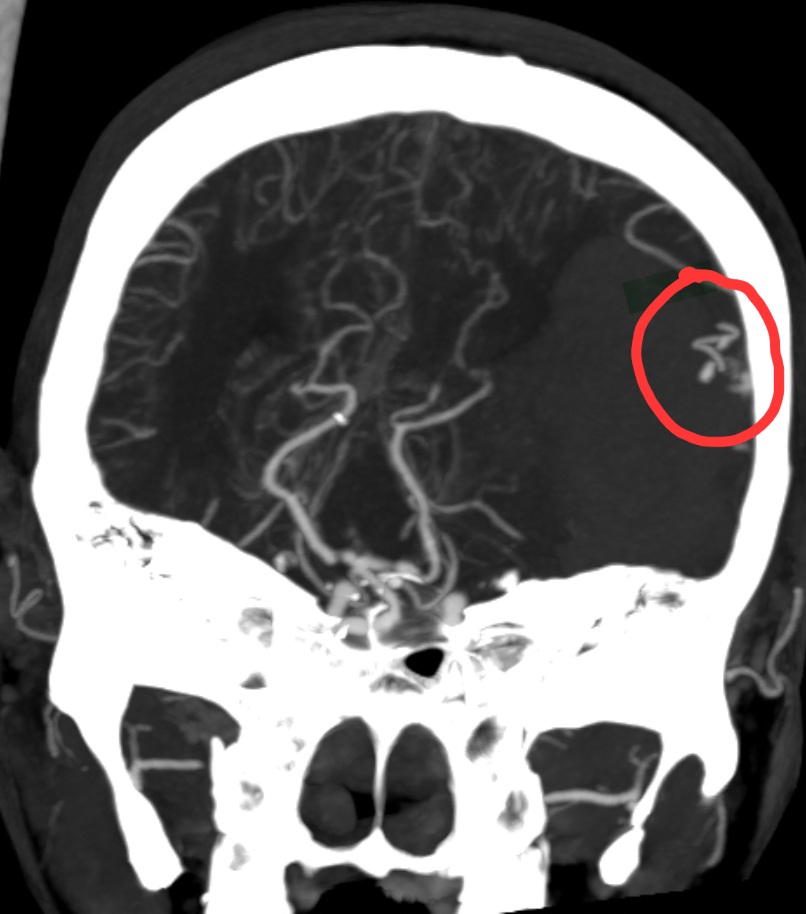

头部CTA提示:左颞顶AVM合并大脑中远端动脉瘤